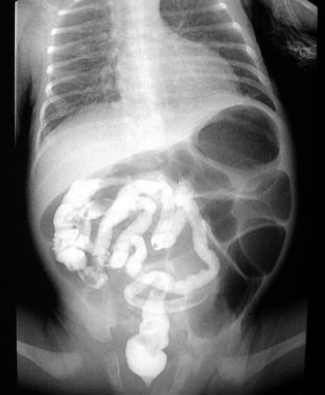

What is the diagnostic test for jejunal/ ileal atresia?

Abdominal x-ray showing air-fluid levels